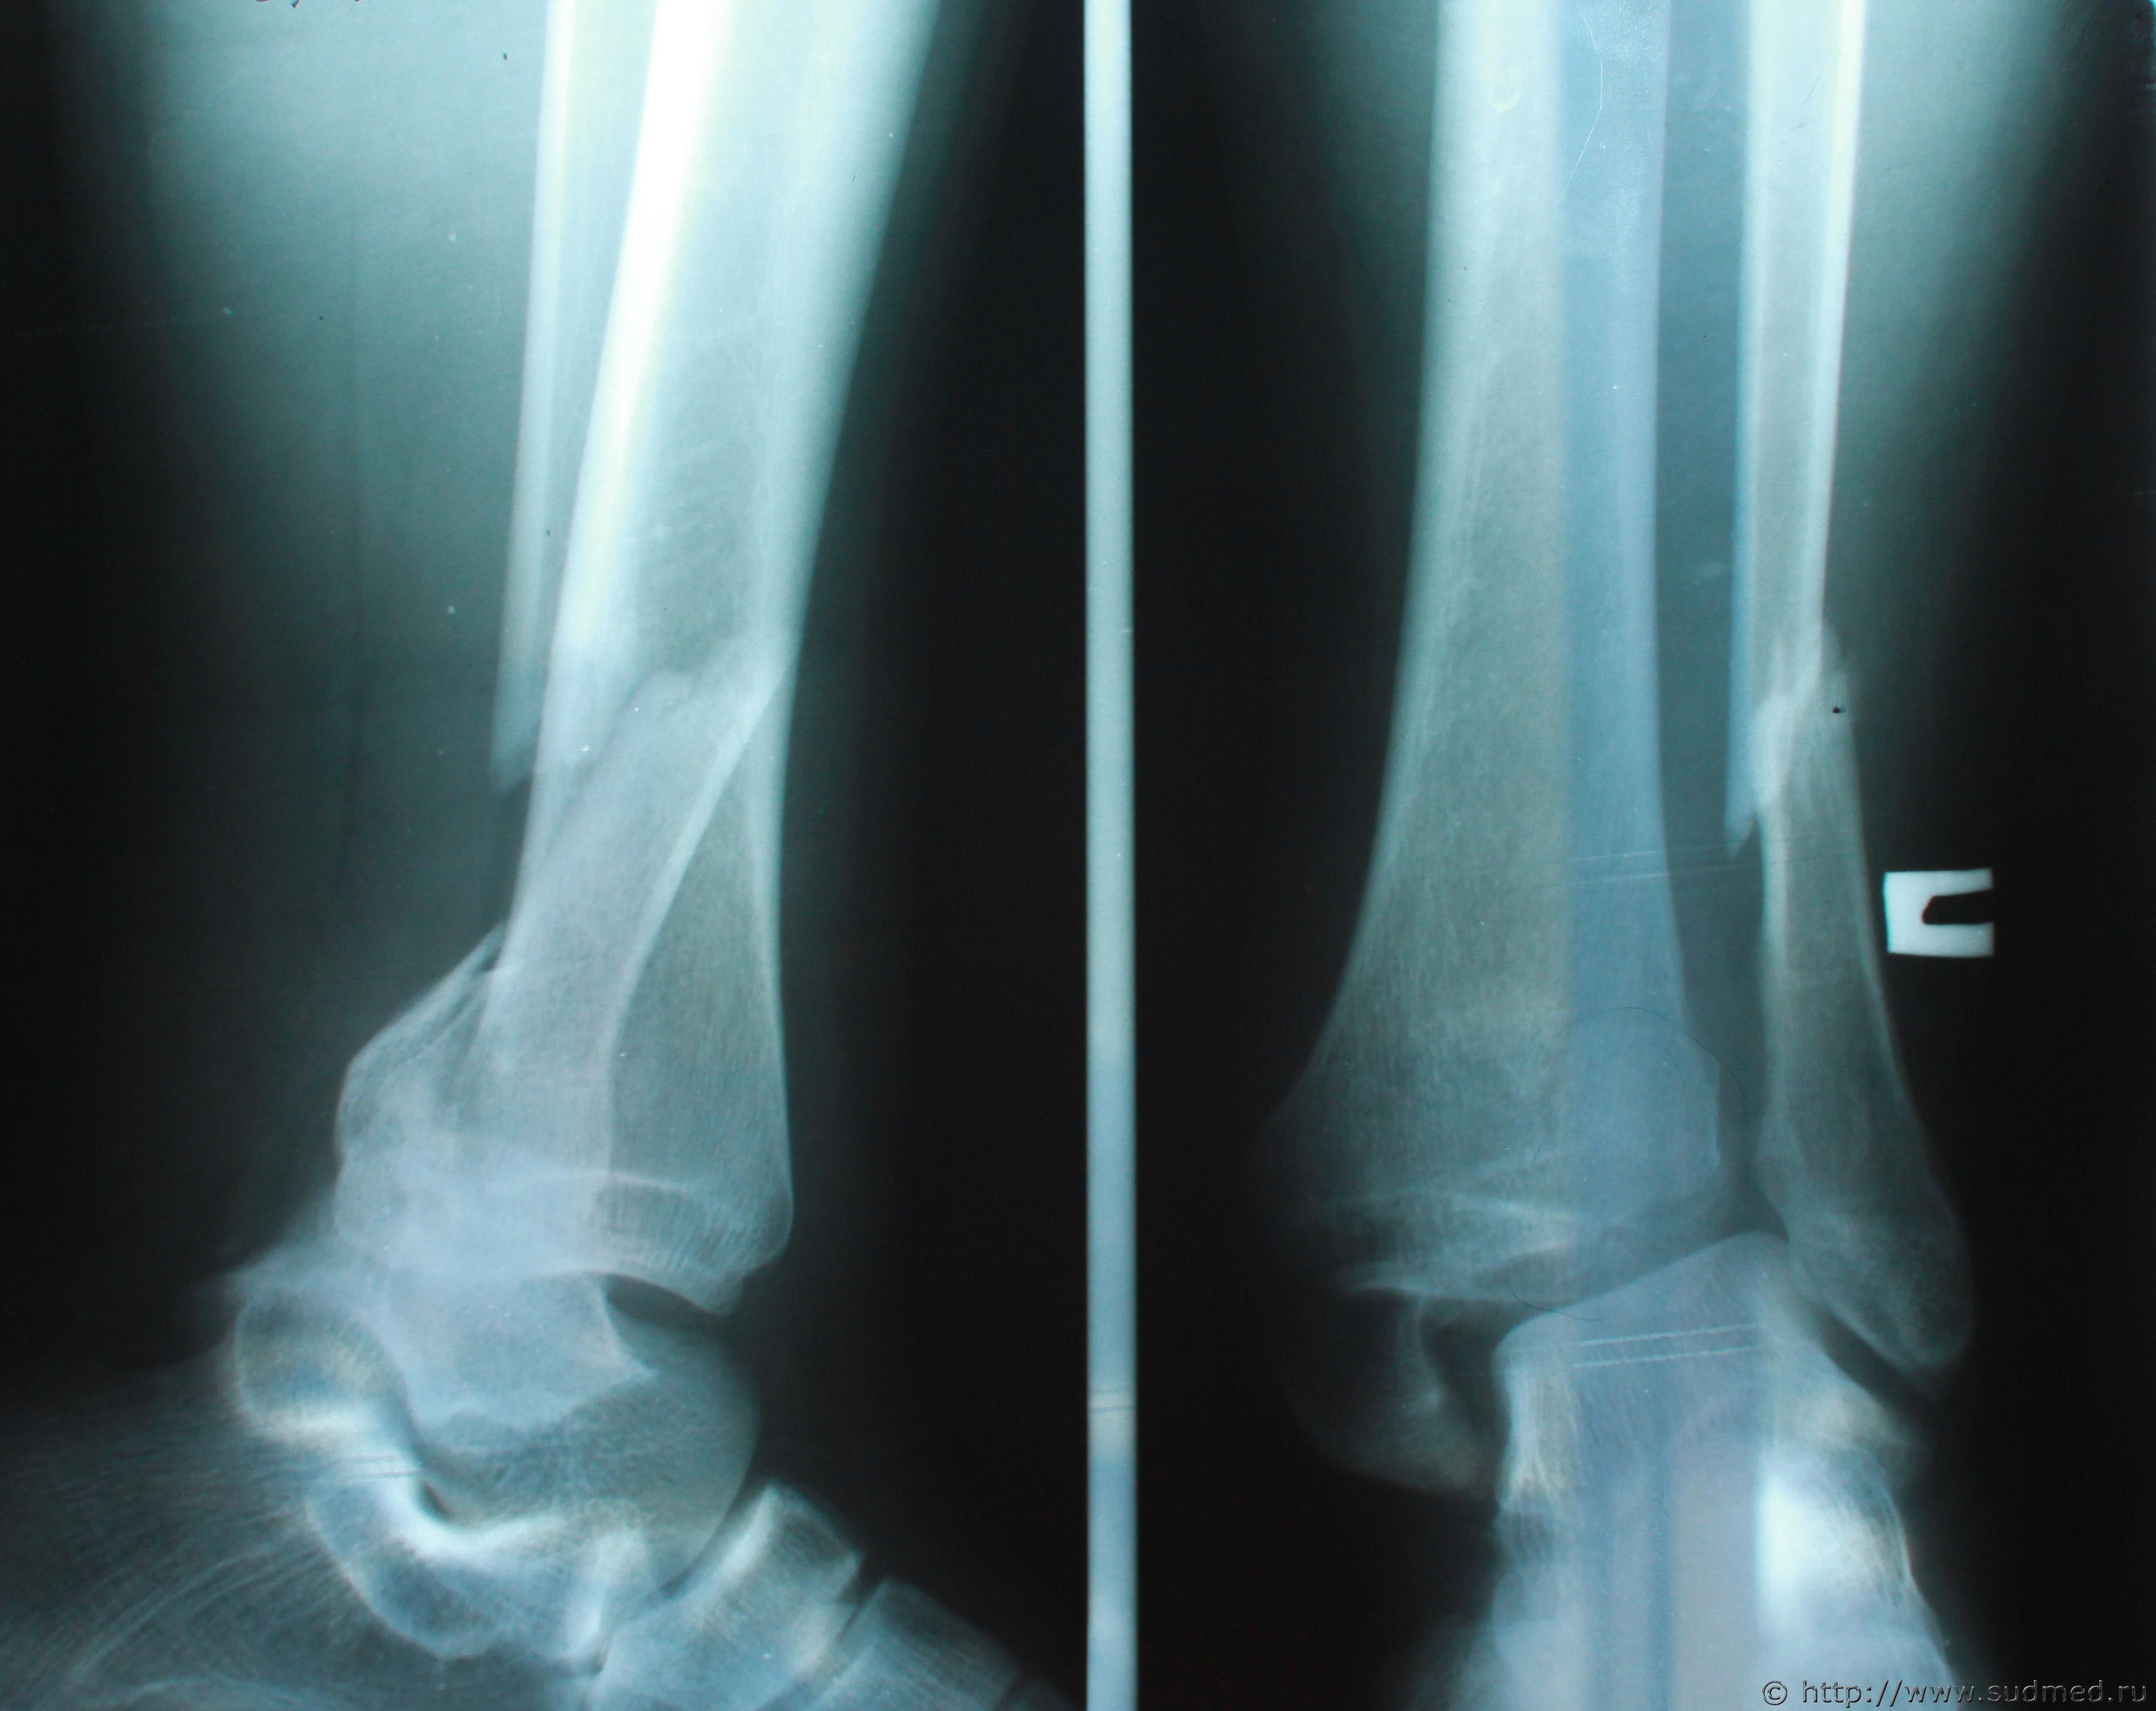

• При обращении за медпомощью у крокодила Гены установлены повреждения - закрытый задний переломо-вывих правой стопы, закрытый оскольчатый перелом правой малоберцовой кости в нижней трети, внутренней лодыжки, заднего края правой болшеберцовой кости со смещением и разрывом дистального синдесмоза. Данные повреждения могли образоваться от действия тупых твердых предметов, конструктивные особенности которых в повреждениях не отобразились, могли образоваться в условиях дорожно-транспортного происшествия.

• Комплекс установленных повреждений по наиболее тяжелому - закрытому перелому обеих берцовых костей с разрывом межберцового сочленения и вывихом стопы квалифицируется как тяжкий вред здоровью.